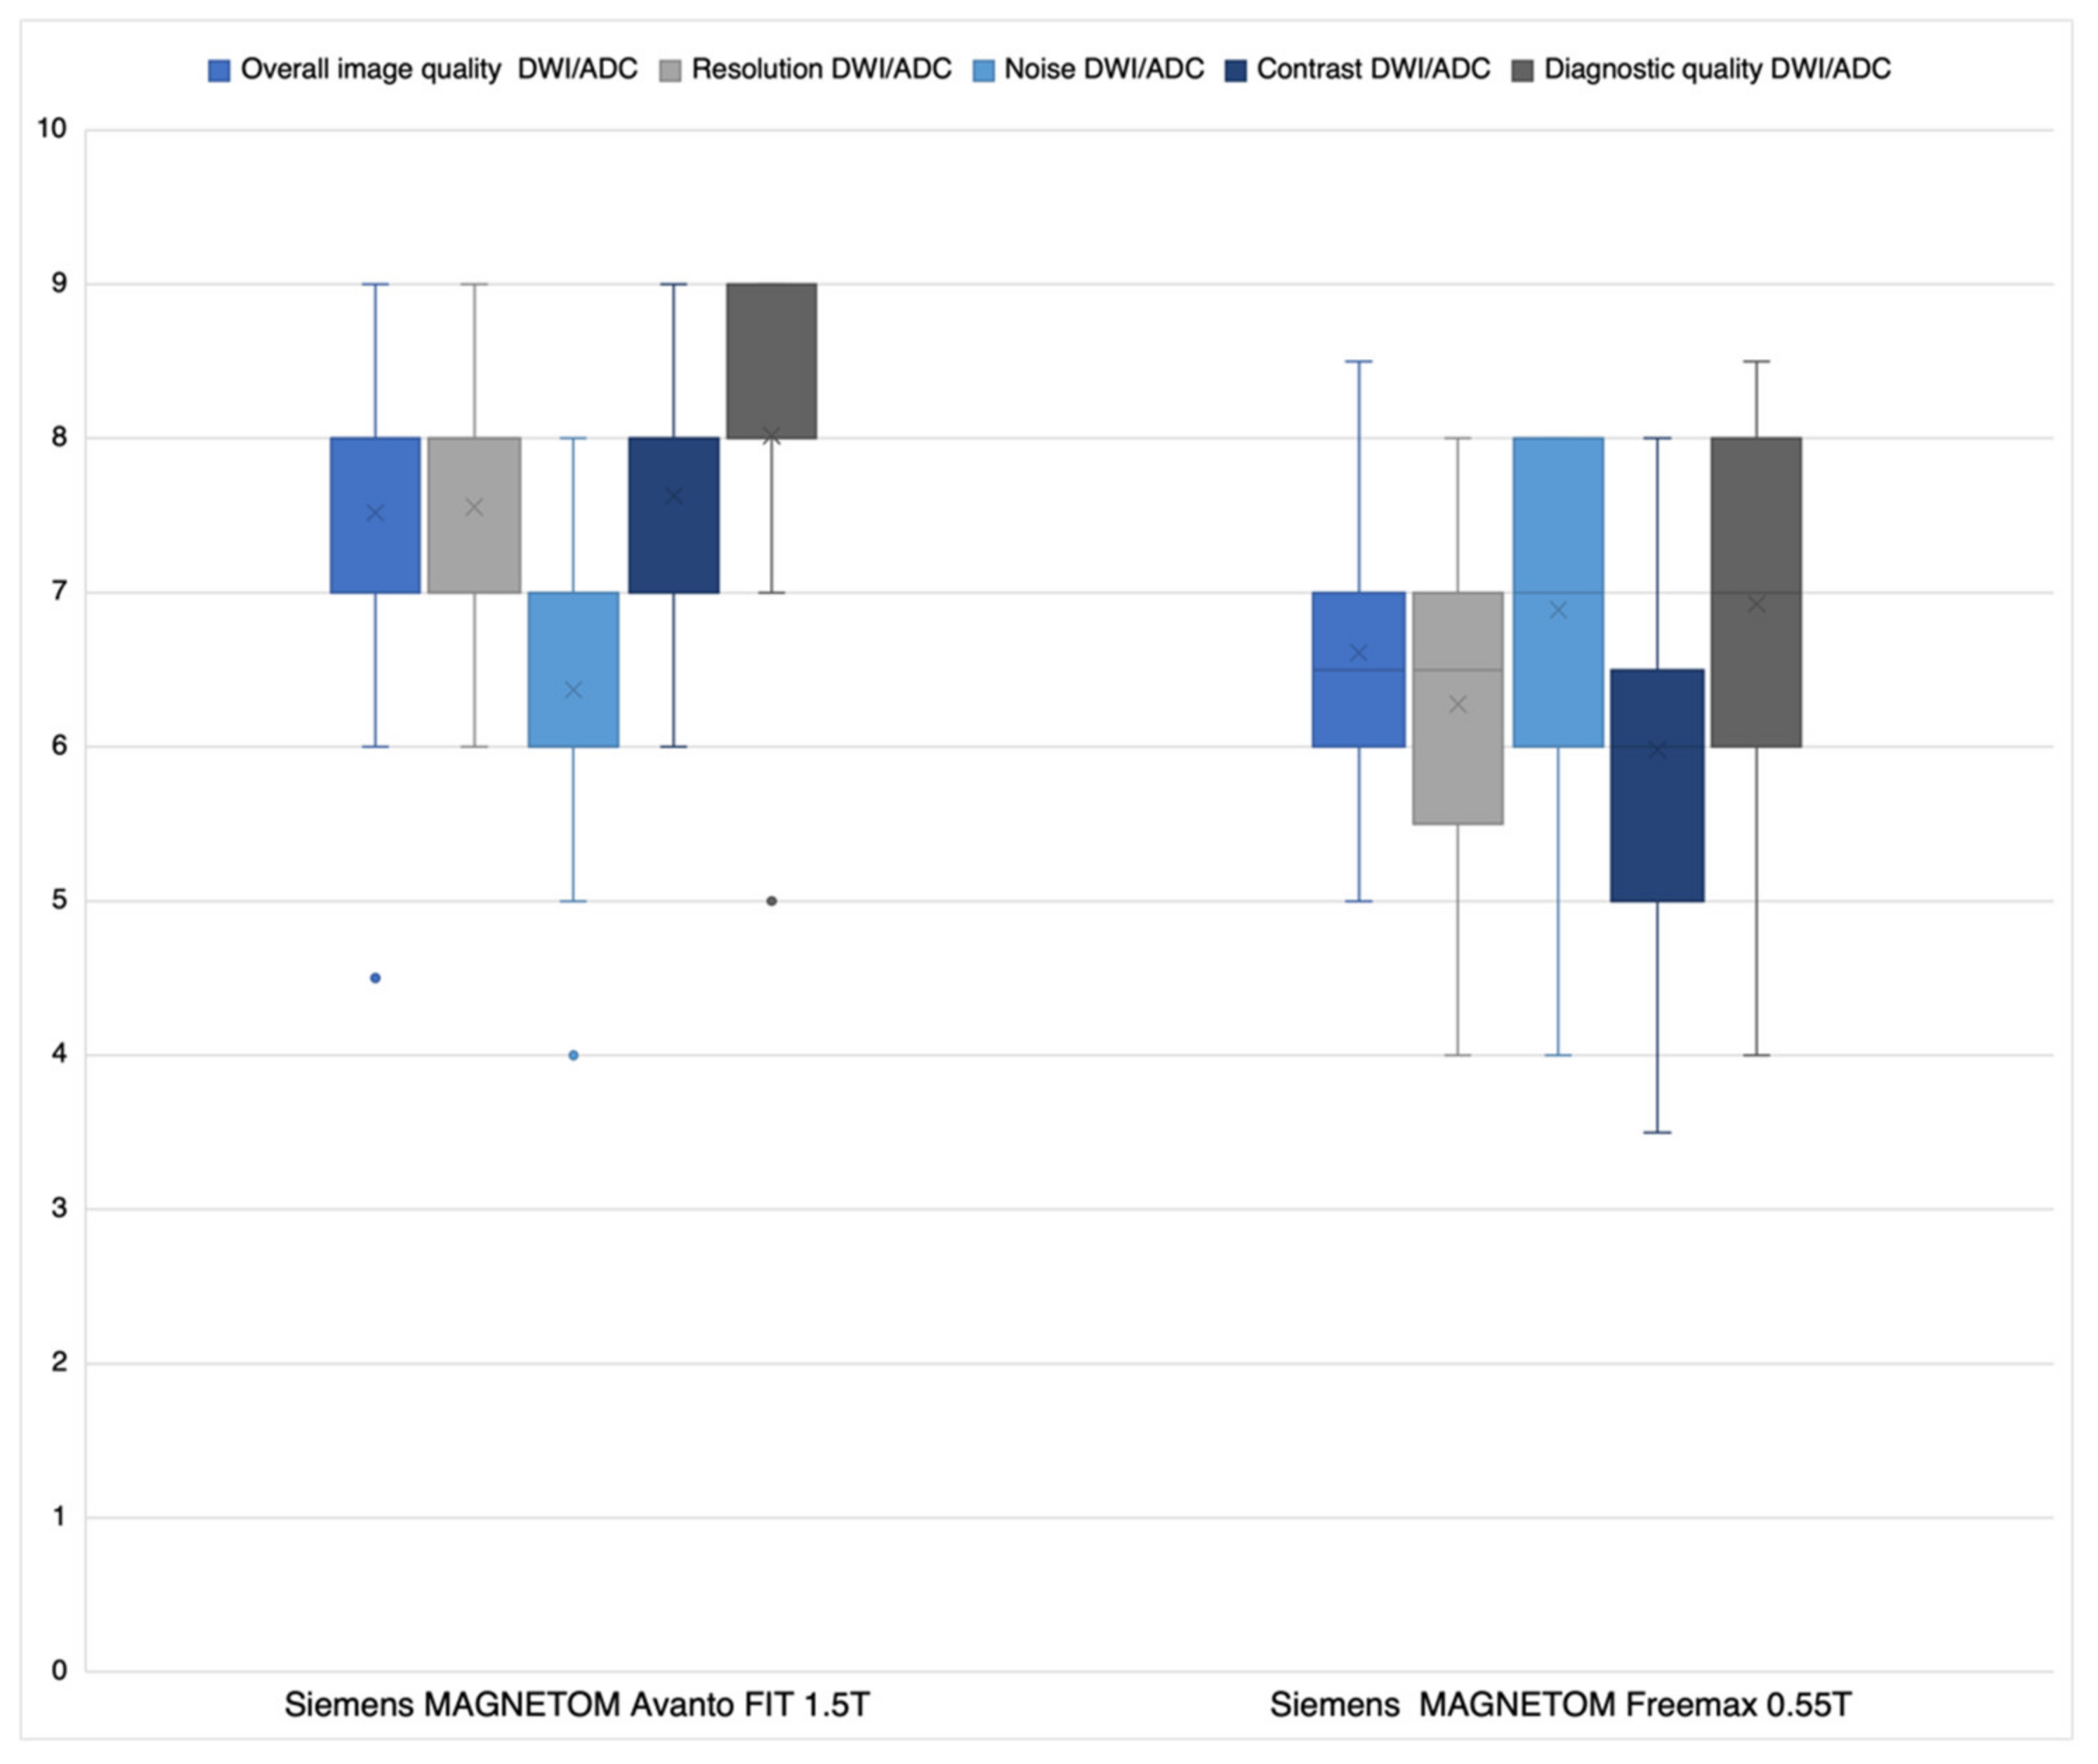

3.1. Likert Rating

3.1.1. DWI/ADC Datasets

4.1. Likert Rating